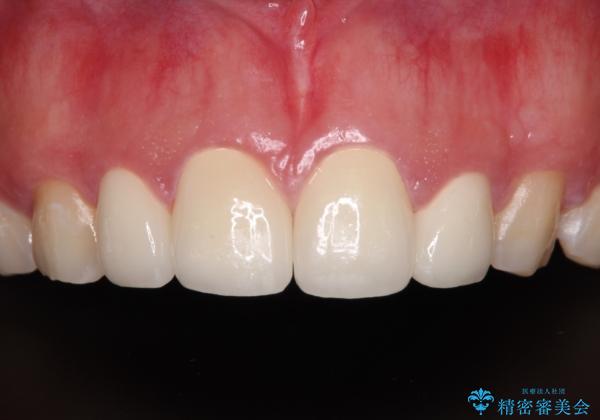

- 前歯の矮小歯と捻れや変色を気にして来院された患者様です。

結婚式が近いということもあり、前歯4本をオールセラミッククラウンにて補綴治療することとしました。

前歯の捻れは、オールセラミッククラウンよりも矯正治療による改善の方が、歯を削らなくて済むためお勧めとなります。

しかし、矮小歯の改善はオールセラミッククラウンでの補綴治療が必要であり、幅径のバランスを取る必要があるため、4前歯の補綴治療を選択しました。